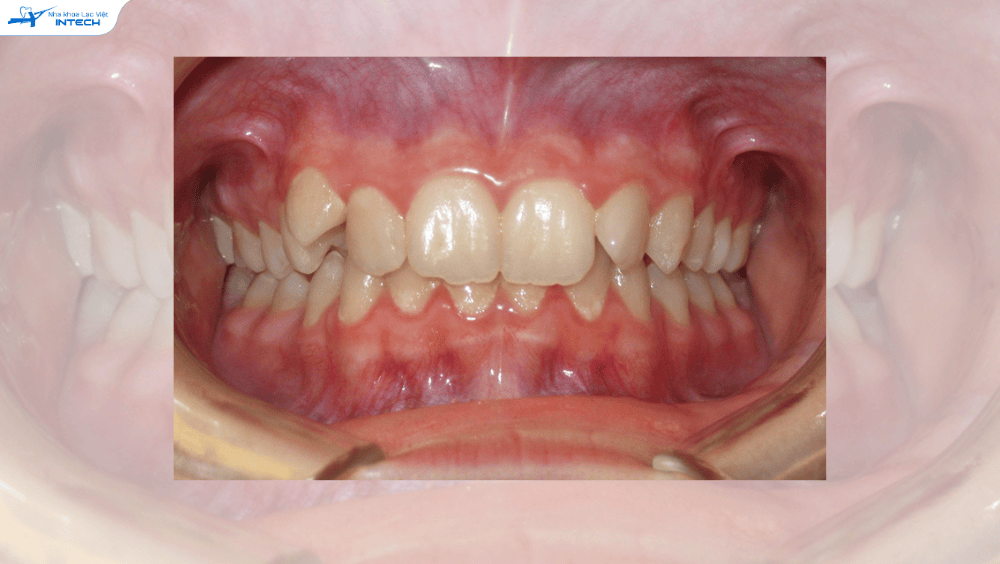

Khách phải nâng khớp khi gặp tình trạng khớp cắn sâu

70% khách hàng Khách hàng bị khớp cắn sâu "nắt buộc" phải nâng khớp